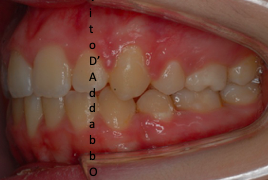

In alcune malocclusioni i denti superiori non coprono adeguatamente quelli inferiori con la presenza in alcuni casi di una beanza fra le due arcate. Questo può essere dovuto ad abitudini viziate come il succhiamento del dito, una deglutizione scorretta, una postura della lingua alterata o un problema scheletrico. In questo esempio il problema è associato ad una terza classe scheletrica.

prima